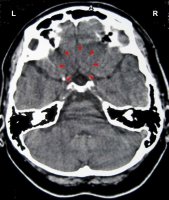

DEVELOPMENT AND FUNCTION OF THE MOUTH AND PHARYNX SUBMUCOSA: The mouth is the opening of the alimentary canal and the place where the digestion (secretory quality) and absorption (absorptive quality) of food starts. The tongue is an accessory digestive organ that aids in chewing and swallowing. Through chewing, food is broken into small pieces. Saliva produced in the salivary glands moistens the food bolus to make swallowing easier. The salivary glands are located in several parts of the mouth. The largest salivary glands are the parotid glands in front of the ears, the sublingual glands underneath the tongue, and the submandibular glands beneath the lower jaw. The pharynx connects the mouth and nasal cavities with the trachea and the larynx. The nasopharynx, located in the back of the nose, extends to the upper surface of the palate which forms the roof of the mouth; the oropharynx is at the very back of the mouth. On both sides of the pharynx lie the tonsils. Branching off the pharynx is the esophagus that carries food from the mouth to the stomach. The submucosa of the mouth and pharynx (including the lips, gums, palate, tongue, salivary glands, tonsils, and throat) consists of intestinal cylinder epithelium, originates from the endoderm and is therefore controlled from the brainstem.

CONFLICT-ACTIVE PHASE: Starting with the DHS, during the conflict-active phase cells in the submucosa of the mouth or pharynx proliferate proportionally to the intensity of the conflict. The biological purpose of the additional cells is to better insalivate a morsel in order to absorb (right half) or expel (left half) it faster. Salivation is stimulated by the autonomic nervous system. This is why the secretion of saliva increases with the smell of “mouth-watering” food. In the English language, “salivating” and “drooling” are synonyms for “craving” for something or someone desirable.

With prolonged conflict activity a flat growth (absorptive type) develops in the submucosa of the mouth. In the palate, salivary glands, tonsils, pharynx, and throat it can also take a cauliflower-shaped form (secretory type). If the papillae of the tongue that contain the taste buds are affected, the additional cells provide an enhanced sense of taste in order to be able to analyze (see sensory quality) the “morsel” (compare with hypersensitivity to taste related to the posterior third of the tongue).

Adenoids in the nasopharynx form as a result of a hanging conflict, that is, when the “scent morsel”-conflict cannot be resolved in time (compare with polyps in the paranasal sinuses). If the tonsils are affected, this causes tonsillar hypertrophy, or enlarged tonsils. Since the tonsils and the nasopharynx share the same brain relay, nasal polyps and enlarged tonsils often occur together.